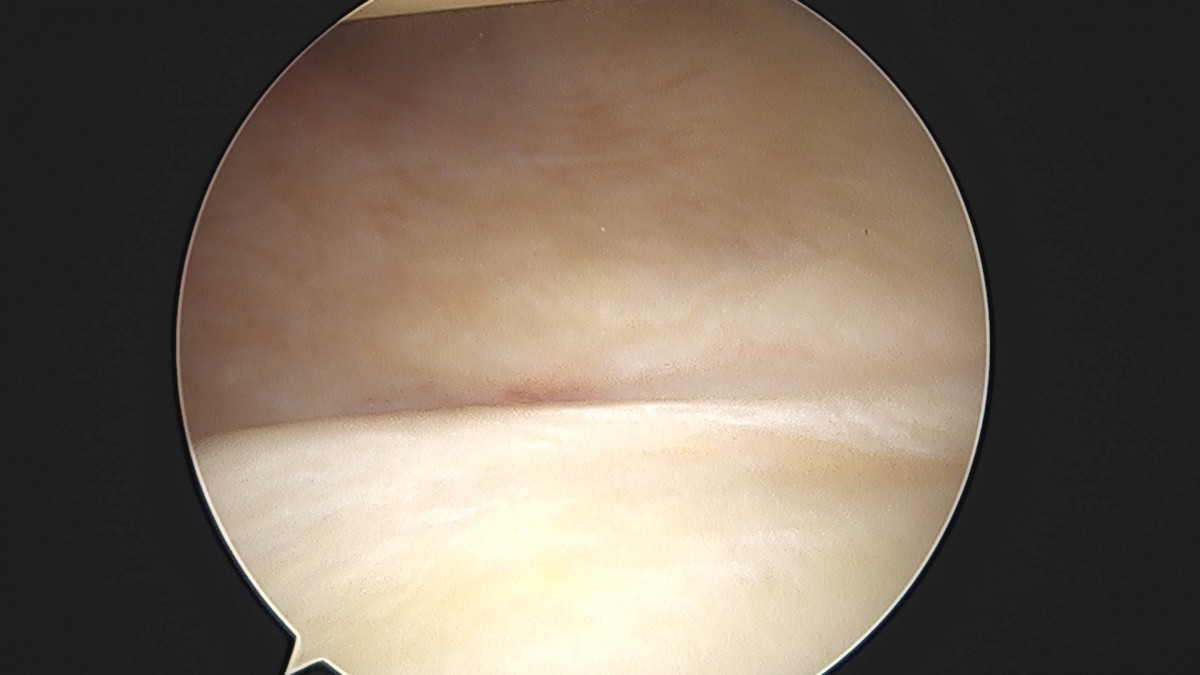

이재상원장님 어깨 견봉하 감압술 및 관절낭 이완술 양명O 환자

작성자 최고관리자 댓글 0건 조회 788회 작성일 25-09-16 15:33